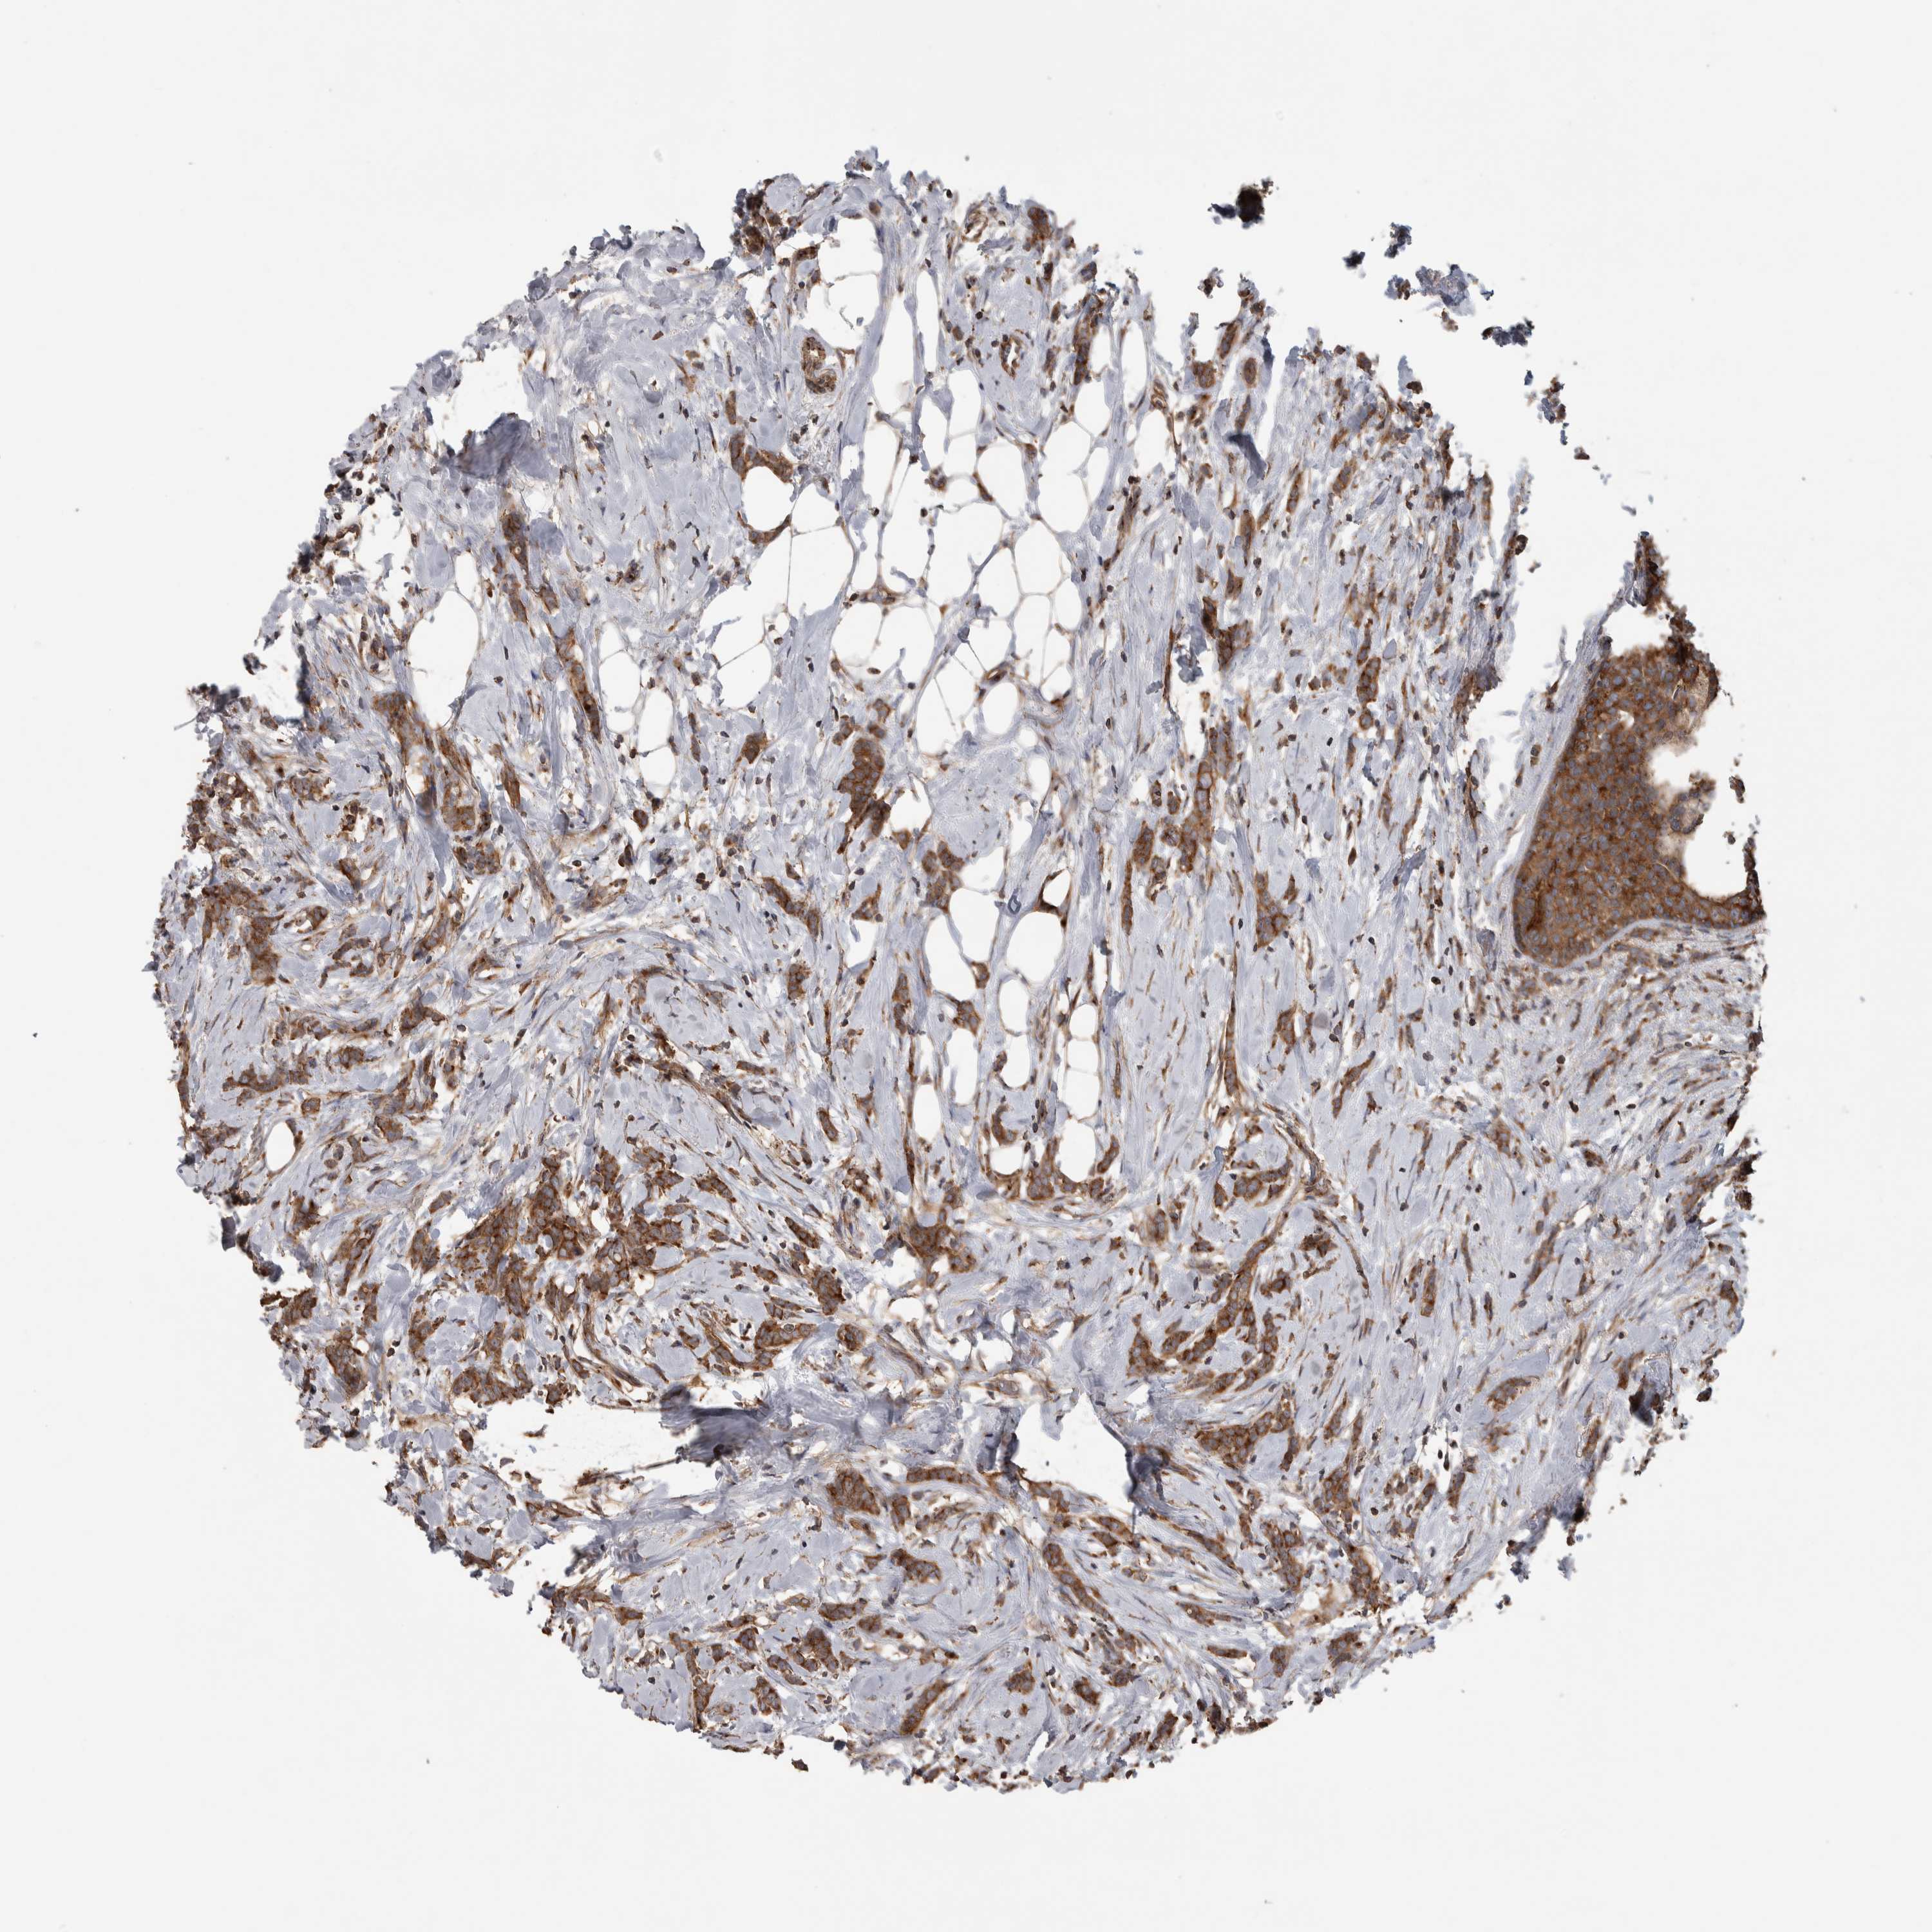

CANCER BREAST CANCER Show tissue menu

BRCA TCGA BRCA VALIDATION PROTEIN EXPRESSION